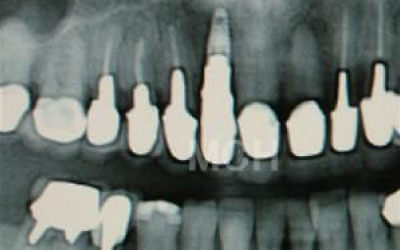

CT撮影を行うことで、骨や歯の状態を立体的に把握でき、各部位の距離を正確に測定することができます。

インプラント治療では、骨の厚さや傾斜、神経の位置などを事前に詳細に確認することで、より安全で確実な治療計画が立てられます。

2. 顎の神経に触れるリスク

下あごの骨の中には神経が通っており、治療の際に誤って刺激する可能性があります。

しかし、事前にCT撮影を行って神経との距離を正確に把握した上で計画を立てることで、リスクは大幅に軽減できます。

さらに当院では、必要以上に骨を削らないよう専用のストッパーも併用しています。

4)骨の状況をしっかり把握するためにも、CT撮影が必須となります。 また、インプラント治療においては、周囲の歯の状況や咬み合わせの問題などもしっかりと考えて治療するのがとても大切です。